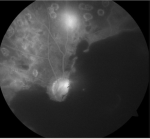

Diagnostic assessment: fluorescein angiography showed masking by hematoma and neovascularization (Figure 2). Optical coherence tomography confirmed subretinal hemorrhage in the left eye (Figure 3) and cystoid macular edema in the right eye (Figure 4 ).

Figure 2: masking effect of hemorrhage with neovascularization and laser marks